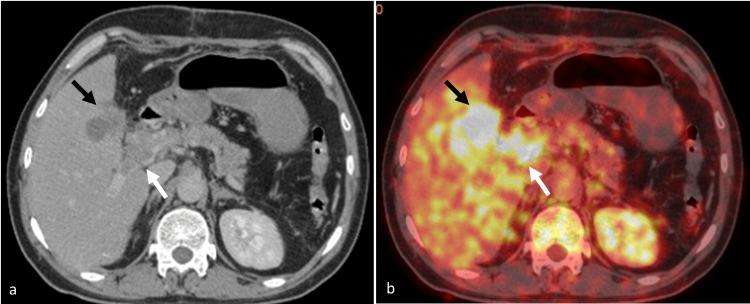

We report a rare case of adenosquamous carcinoma of the gall bladder (GB) causing portal vein tumor thrombus. A 40-year-old gentleman presented with acute-onset right upper abdominal pain. Ultrasonography revealed multiple calculi in the GB with wall thickening, suggesting acute cholecystitis. Intraoperatively, irregular wall thickening of GB with infiltration into the duodenum and stomach was found. Partial cholecystectomy was performed, and a histopathological examination of the resected specimen revealed adenosquamous carcinoma. PET-CT revealed a fluorodeoxyglucose (FDG)-avid lesion in the GB and the main portal vein, suggesting a tumor thrombus. Two weeks later, he developed jaundice, and contrast-enhanced CT (CECT) showed a heterogeneously enhancing mass in the GB fossa, encasing the main portal vein, with an enhancing filling defect within its lumen, suggestive of tumor thrombus. Multiple periportal and peripancreatic lymph nodes were seen, encasing the common bile duct and causing intrahepatic biliary radical dilation. Percutaneous transhepatic biliary drainage was performed, and palliative chemotherapy was started.

摘要